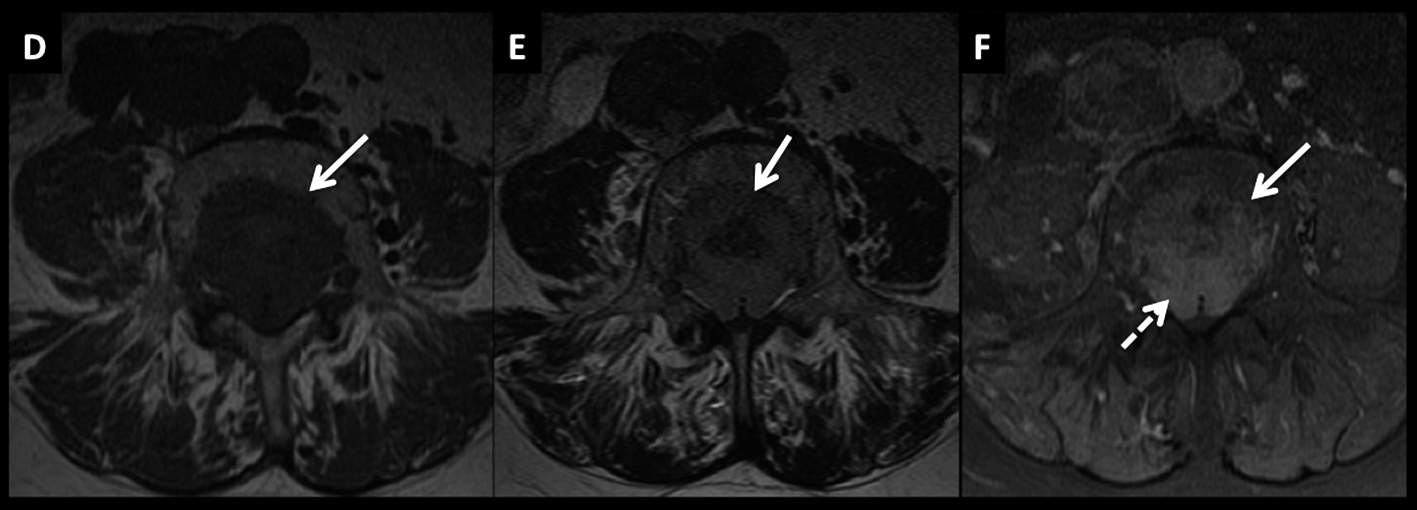

Figura 4

LNH, lesiones óseas y masa extradural, compromiso secundario. (cont)

En el plano axial (D secuencia T2, E secuencia T1 y F secuencia T1 con contraste) se observa la masa descrita con un patrón de crecimiento que lo “amolda” al canal y se extiende a los espacios vecinos a través de los neuro-forámenes del nivel seleccionado.